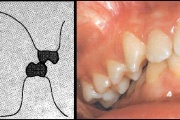

) Röntgenülesvõte. Ülemise esimese jäävmolaari lõikumine on takistatud 2. piimamolaari tõttu

Esimese jäävmolaari ektoopiline lõikumine

Ravijärgne seis. Jäävhammas on täielikult lõikunud.